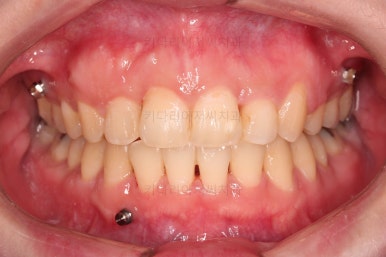

4. 마무리

치료 종료 시 입안의 모습입니다.

윗니만 발치를 했지만 교합이 잘 맞고요.

한 쪽 송곳니가 없지만 기능적으로 전혀 문제를 못느끼실 교합을 맞춰놨고요.

위아랫니 가지런해졌고요.

대신 중앙선은 약간 틀어져 있는데요.

한 쪽은 송곳니가 없고 한 쪽은 작은 어금니를 발치했기 때문인데요.

18개월이라는 짧은 기간동안 부정교합, 덧니, 심지어 매복치아까지 개선했는데 양측 치아 사이즈 문제로 생기는 중앙선 정도는 아무 문제가 안되는거죠.